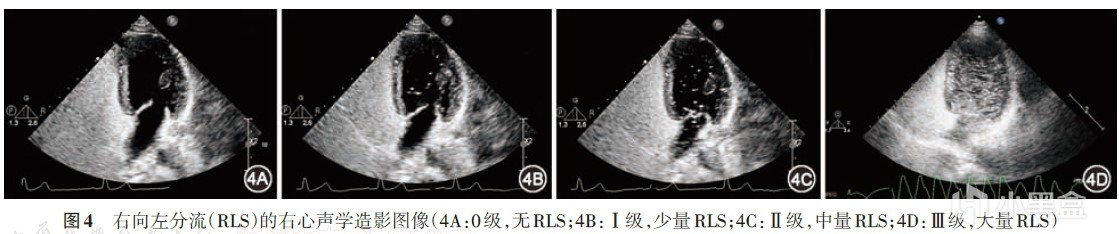

其實就是我評論裏說的發泡試驗,準確說是指經顱多普勒超聲聲學造影(cTCD),目前也有經胸超聲心動圖右心聲學造影(cTTE)。

簡單說就是將含有微氣泡生理鹽水作爲造影劑,因振盪微氣泡不能通過肺毛細血管網,只能顯示右心腔,可清晰顯示PFO處分流的大小及方向,故可藉此判斷是否存在心內分流及肺內分流。

將含有微氣泡生理鹽水注射到體內,同時做Valsalva動作,就能在彩超下判斷是否有PFO了。

![]()